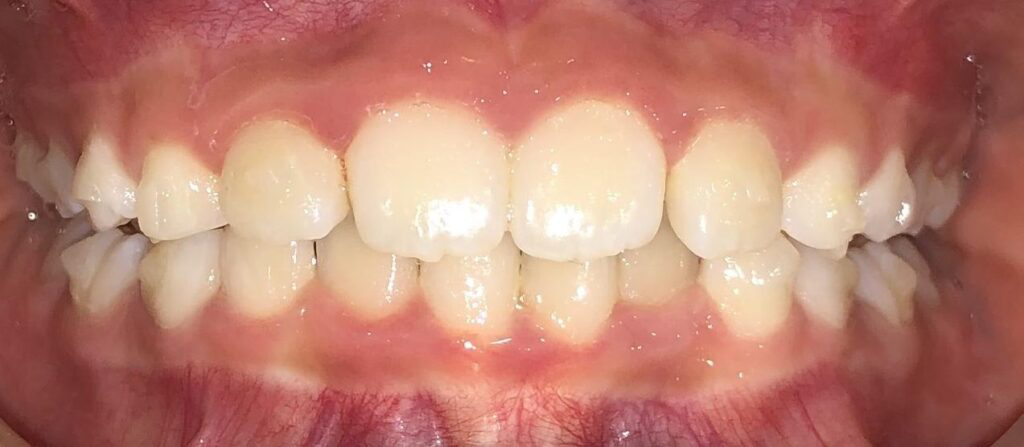

Actual Patient: Victoria

Img Before 1 1 Img After 1 1

Severe Crowding, Narrow Jaws, Severe Deep Bite

image 1 after img

Treatment Time:

8 months

Front View

Top View

Right & Left Sides